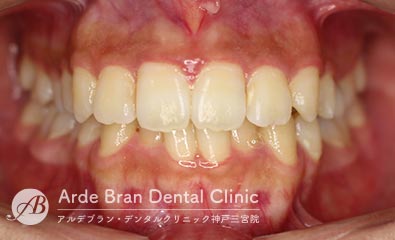

- 叢生/八重歯/歯のがたつき(20代女性 治療期間2年)

- 上下の犬歯の突出と歯のがたつきを主訴に来院されました。特に上下ともに犬歯が大きく前に出ており、噛み合わせに悪影響を及ぼしている状態でした。歯列のスペース不足が顕著であったため、上下左右の第一小臼歯を4本抜歯し、適切な歯列を確保する方針としました。治療では、上下の犬歯を正しい位置へ誘導しながら、全体の噛み合わせを調整。歯列のアーチを整え、前歯のねじれやガタつきも改善しました。治療後は、上下の犬歯が適切な位置に収まり、口元のラインがすっきりと改善。歯並びだけでなく、噛み合わせや清掃性の向上にもつながり、機能的で美しい口元を実現しました。

- 治療前

- 治療後

| 装置名 | インビザライン(マウスピース矯正) |

| 抜歯非抜歯 | 4本抜歯 |

| 治療期間 | 2年 |

| 費用 | インビザラインフル72万円+TAX |